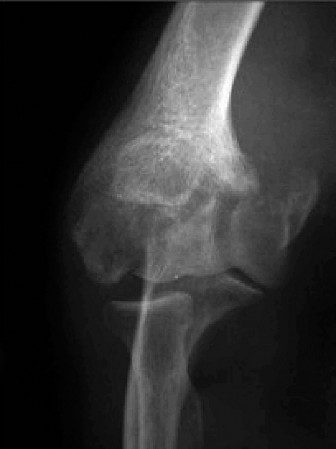

Standard Radiographs:

- Anteroposterior (AP) and Lateral Views: Essential for assessing joint space narrowing, osteophyte formation (anterior coronoid, posterior olecranon, radial head), subchondral sclerosis, loose bodies, and overall alignment.

- Oblique Views: To better visualize specific compartments.

- Capitellar View (Greenspan): Useful for assessing the capitellum and radial head.

Computed Tomography (CT) Scan:

- Crucial for PTEA: Provides detailed 3D bony anatomy, excellent for delineating osteophytes, identifying and localizing loose bodies, assessing malunion of previous fractures, and evaluating bone stock, particularly for arthroplasty planning. CT with 3D reconstructions can precisely map sites of impingement and guide osteophyte resection.